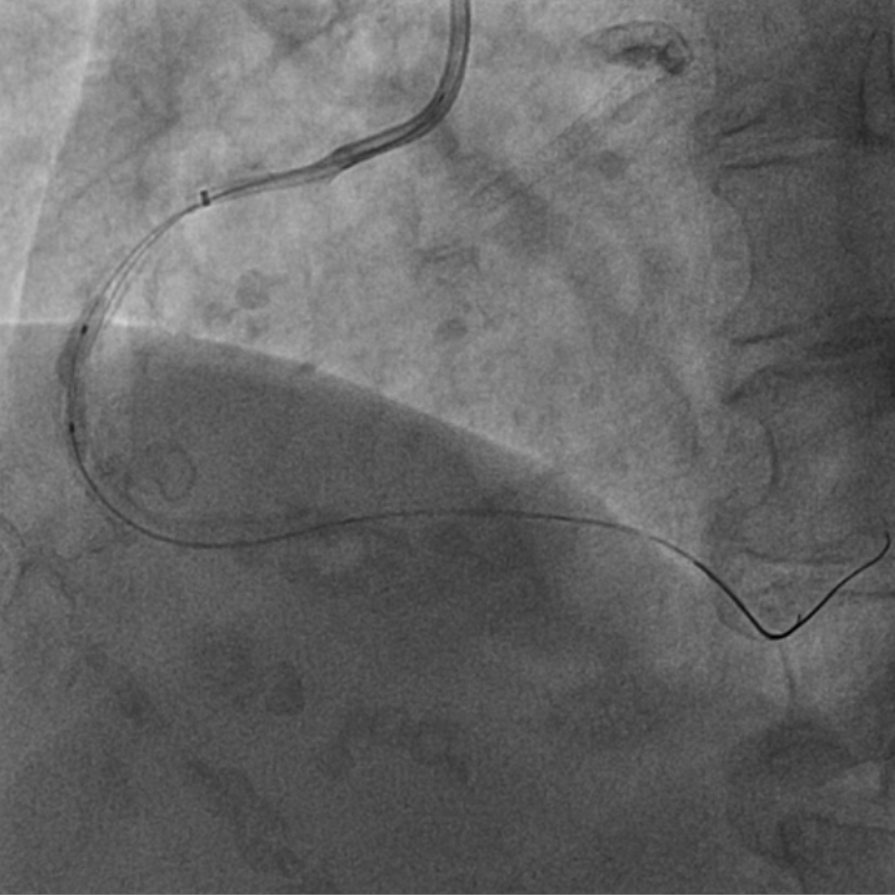

图2 术前造影提示多处再狭窄,冠脉钙化明显

该患者入院后,完善相关检查并再次建议行CABG治疗,但家属仍拒绝,遂考虑再次行PCI手术干预。冠脉造影提示患者冠脉右冠状动脉中段70-95%再狭窄,左主干末端80%狭窄,前降支原支架中远段 80-95%再狭窄,回旋支完全闭塞,急需手术尽快解决冠脉血流灌注问题,否则随时有生命风险,但患者多处支架内/节段内再狭窄,造影提示钙化明显,外院已尝试无法扩张,经手术团队充分讨论后,计划在IABP支持下,先进行右冠状动脉干预,利用IVUS精准评估原支架再狭窄部位情况,采用旋磨或Shockwave冲击波球囊处理无法扩张的病变部位,右冠处理后择期进行左冠状动脉干预。在制定了详尽的手术计划后,手术团队首先对患者的右冠状动脉行IVUS检查,结果提示该患者右冠中段支架局部膨胀不良,局部支架面积6.67mm²,管腔内多处可见钙化小结及270°以上钙化,IVUS钙化积分达3分。由于膨胀不良处原支架后方可见钙化斑块,常规旋磨效果不佳,对于此类钙化病变,IVL处理是最佳方案。手术团队对近端采取棘突球囊及高压球囊进行扩张,采用Guidezilla辅助下输送3.0mmx12mm Shockwave冲击波球囊于右冠钙化处进行冲击波钙化斑块碎裂术,通过IVUS证实支架内的新生钙化病变得到松解,原膨胀不良部位支架面积达到7.76mm²,后经过高压球囊充分预处理,顺利完成右冠支架植入,术后复查右冠原膨胀不良部位支架面积9.17mm²。